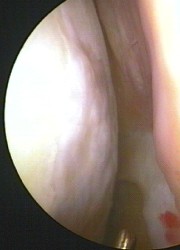

Der Organismus betrachtet das implantierte Material nicht als Fremdkörper. Es verfügt über ähnliche biomechanische Eigenschaften wie der natürliche Knorpel.

Die lebenden Chondrozyten sind so in der Lage, wieder für den Aufbau einer funktionierenden Knorpelschicht zu sorgen. Da die in Kugelform gezüchteten Knorpelzellen (sog. Sphäroide) direkt an die Stelle im beschädigten Gelenk gesetzt werden, an der die Knorpelmasse fehlt, vermehren sie sich unmittelbar dort, wo der Knorpel benötigt wird. Es entsteht gesundes körpereigenes Knorpelgewebe, das all die schützenden Funktionen wieder erfüllt, die dem geschädigten Gelenk gefehlt haben.

Bereits nach ca. sechs Wochen zeigt sich eine vollständige Bedeckung des Defektes mit lebenden Knorpelzellen, die jedoch noch nicht die Dicke und Belastbarkeit des umliegenden Knorpels besitzen. Vergleichbar mit einem frisch eingesäten Rasen, auf dem zum Schutz der jungen Pflänzchen auch nicht sofort Fußball gespielt werden darf, sollte auch der Knorpel in dieser Zeit noch nicht voll belastet werden. Um der Knorpelfläche die nötige Zeit zur Regeneration zu geben, kann der Patient Unterarmgehstützen zur Entlastung verwenden. Gleichzeitig ist auf eine ausreichende Bewegung des Gelenks zu achten, damit durch die Wechseldruckbelastung die Durchblutung angeregt wird. Die Ernährung des Knorpels erfolgt durch Diffusion – ähnlich wie bei einem Schwamm. Wird dieser zusammengepresst, treten Schlackenstoffe aus und bei Entlastung werden dagegen Nährsubstanzen aufgenommen. Spezielle Bewegungsschienen und Physiotherapie unterstützen die Heilung.